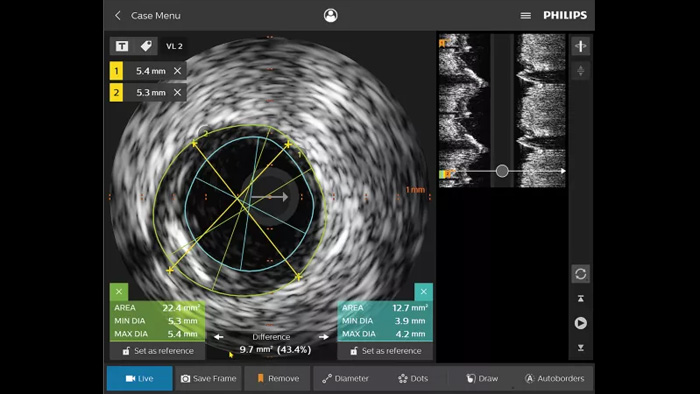

血管内超音波検査(IVUS)はカテーテルベースのイメージング技術であり、これを利用して医師は内部から血管を視覚化して、疾患の有無と程度を評価することができます。IVUSは、患者ごとに適切なインターベンション治療の選択、支援、そして確認に役立ちます。